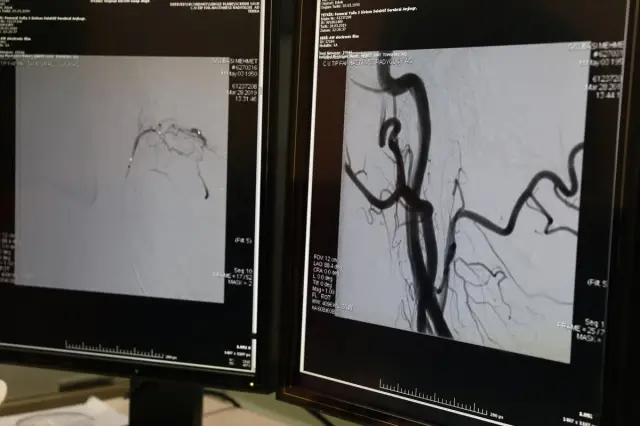

Hastanın MR ve anjiyo grafik tetkiklerinde beyin damarında kıymetli kaçak tespit ettiklerini aktaran Yıldız, “Halk ortasında kaçak denilen atar damar ile toplardamar ortasında kanın karışmasını anlatan bir durum. Daha sonra bunu tedavi planlamasına aldık ve hastanın ameliyatını kapalı teknikle gerçekleştirdik.” sözlerini kullandı.

“Bu tedaviler kendi içerisinde birtakım riskler içeriyor. Uygun gereçlerle damar içi yoldan endovasküler teknikle kaçağını kapattık. Daha sonra nöroloji servisinde muayene ettiğimiz hastanın bacaklarında kısmen bir düzgünleşme olduğunu gördük. Bu da bizim yaptığımız tedavinin tesirli olduğunu gösteriyor. Bundan sonraki süreçte hastanın genel ve fizik tedavisi yapılacak, denetimlerle birlikte hastanın tetkiki pahalandırılacak. Bu tedavi üniversitemiz için çok kıymetli zira daha evvel Sivas’ta bu teknikte bir ameliyat yapılmadı. Bilhassa spinal teşebbüs olarak kıymetli bir tetkik ve teknik. Bu açıdan gururluyuz, bu düzeye ulaşmak kolay değil. Çok büyük bir birikim gerektiriyor.”